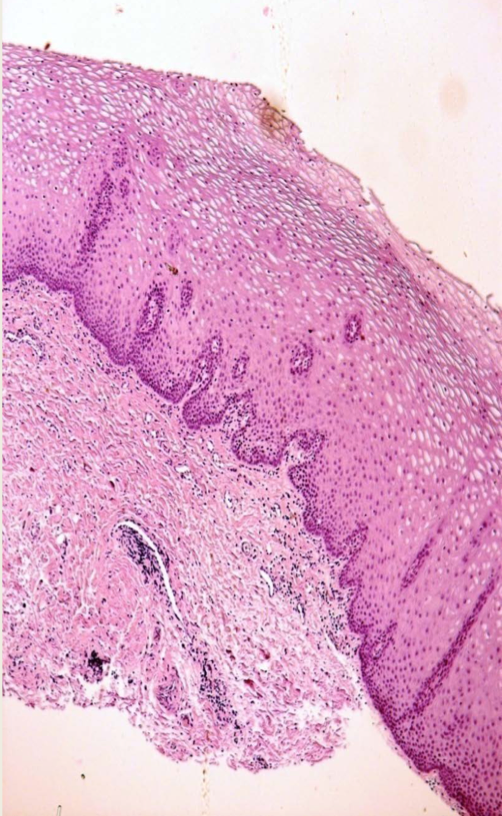

Histopathology of leukoedema

Epithelium: parakeratotic and acanthotic

Spinous layer: intracellular edema

Enlarged cells with lots of clear cytoplasm and small nucleus